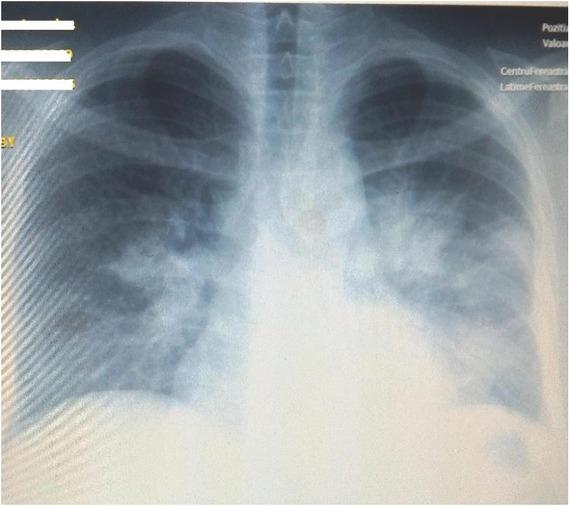

Chest X-ray at admission evidenced multiple diffuse opacities distributed in the half inferior part of both lung areas, suggestive of bilateral bronchopneumonia (Figure 1).

Initial chest X-ray: multiple diffuse opacities distributed in the half inferior part of both lung areas, suggestive of bilateral bronchopneumonia.